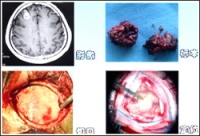

脑血管畸形--病灶

脑动静脉畸形有以下典型表现:①显示畸形血管。这是特征表现,呈一团管径相仿相互纠缠的迂曲扩张血管。畸形血管团的范围可小如指甲,大如手掌,多见大脑半球皮质.②异常粗大的供养动脉和引流静脉伴局部循环加快。此为局部血流短路的表现。③血流分流现象:造影剂随血流经畸形血管的短路大量流入静脉,因此,血管畸形部分因血流量增加而显影十分清楚。④血肿的表现:血管破裂出血致脑内血肿,血肿的主要表现为局部占位征象,一股脑部动静脉畸形无血肿时,脑血管不出现占位征象,脑血管不移位。

CT表现[编辑 | 编辑源代码]

在脑动静脉畸形未破裂出血前有较典型的CT表现。在平扫,可见

局灶性高低或低等混杂密度影,呈斑点、团块或条索状,边缘不清。其中高密度影为局灶胶质增生、血栓、钙化、新出血或畸形内缓慢血流和含铁血黄素沉着所致,低密度影则为小梗塞或陈旧出血,病灶周围有局限脑萎缩,没有明显占位效应,无周围脑水肿。部分病人平扫不能发现动静脉畸形,但注射造影剂,方能显示病灶。注射造影剂后,脑部动静脉畸形呈团块状强化,甚至可见迂曲血管影、供血动脉和引流静脉出血后的脑动静脉畸形则出现脑内血肿,蛛网膜下腔及脑室系统出血。根据出血时间长短表现高密度影、混杂密影及低密度影,血肿周围有低密度水肿区。同时有脑室受压变形及中线移位等占位效应。注射造影剂后,部分血肿边缘可出现畸形血管迂曲强化影,同时混杂密影血肿常有环状强化。